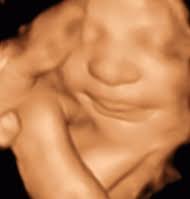

Last 2 week, checkup combined clinic di Hospital Putrajaya. Magikanya kali ni dapat doc yang sama. Bolehla pulak kali ni scan doc cakap mcm nampak bb girl la. Biar betul doc??Okla..mama pasrah dan redha apa jua jantina adik Sofea kali ni, asalkan baby sihat walafiat.